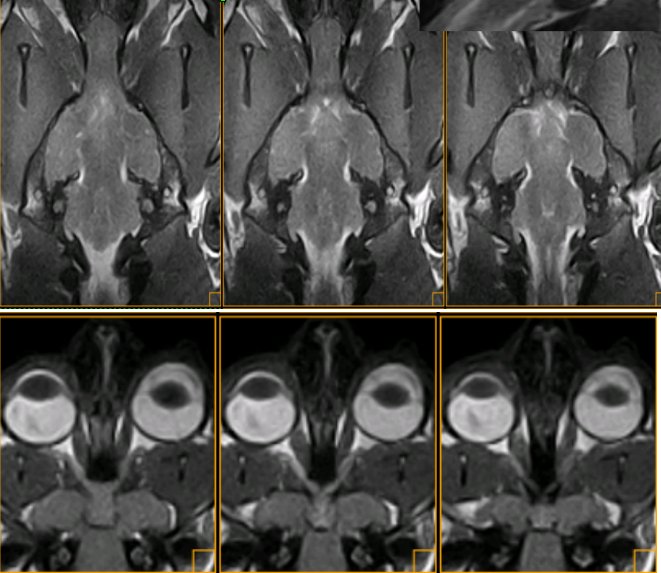

Vía óptica. Cocker. Nervio óptico (n), quiasma óptico (o) Se muestran 4 secuencias de resonancia magnética, en positivo (las de arriba) y en negativo (las de abajo) A: SE T2 dorsal. B: SE T1 transversal. C: SE T1 sagital. D: SE T1 oblícuo, siguiendo la trayectoria del nervio óptico izquierdo, del cual se visualiza perfectamente su entrada por el agujero óptico del esfenoides.